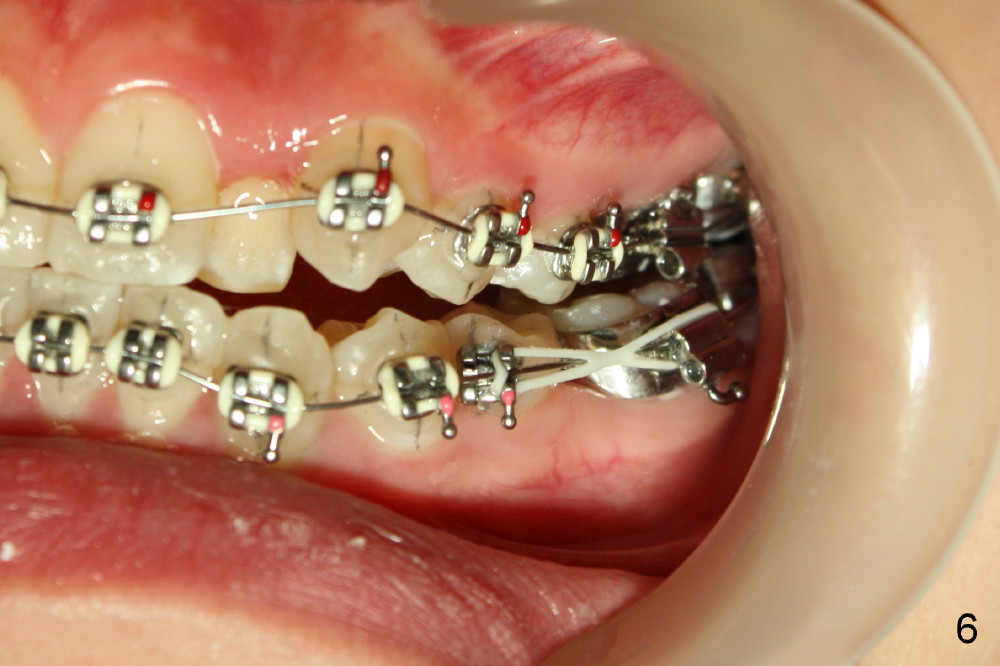

The rotation of LL5 is so severe that the bracket is forced to be placed distal to the height of contour due to interference of LL4 (Fig.4). Because of delayed eruption of L3s (Fig.5: 3), the first niti wires (.014") are bent the most around them. Power chain x2 are placed between L5 and 6 (Fig.6) to correct the rotation of the former in timely manner.